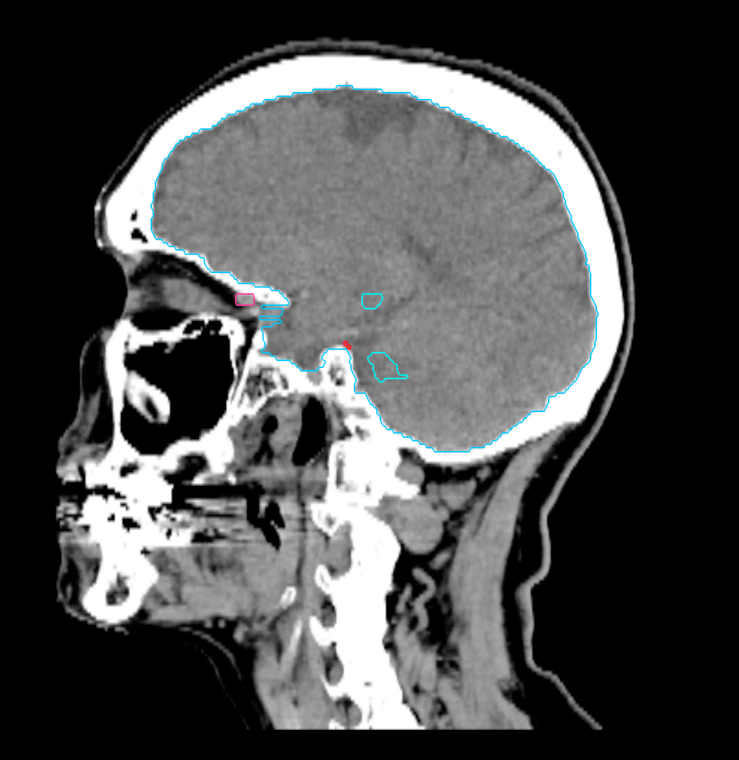

Planning CT Images